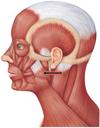

Joints: TMJ & Muscles of Mastication Flashcards

What are the muscles of mastication?

- masseter

- temporalis

- medial pterygoid

- lateral pterygoid

Masseter

COURSE:

- zygomatic arch (deep) + maxilla (superficial) > coronoid process/ramus of mandible

ACTION:

- closes/elevates mandible

- protracts jaw

Temporalis

COURSE:

- temporal lines > coronoid process of mandible

ACTION:

- elevates mandible

- retracts mandible